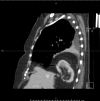

Intrathoracic kidney is a very rare finding, representing less than 5% of all renal ectopias. Because of the location of the liver, thoracic kidney on the right side is much less common than thoracic kidney on the left side. Although an increasing number of case reports are being published in the literature, few describe the impact of the ectopia on kidney function. We report the case of a woman with intrathoracic right kidney and chronic kidney disease that was initially misdiagnosed as pneumonia because of its presentation on chest x-ray. We highlight the need to including this condition in the differential diagnosis[2] as the literature rarely links it to changes in kidney function.

Learning points: Intrathoracic kidney is an extremely rare condition that should be considered in the differential diagnosis of intrathoracic masses.There is a lack of literature on this type of kidney ectopia and its consequences in asymptomatic individuals.